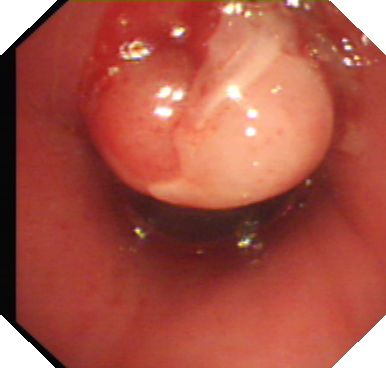

手术在全麻下进行,为使手术操作不影响患者通气,气管插管通过气切口插入气道进行机械通气,支气管镜则经鼻进入到达气道内病灶处,先后反复运用高频电圈套、电凝、活检钳钳夹等介入方法逐渐将肉芽组织切除取出。

高频电圈套